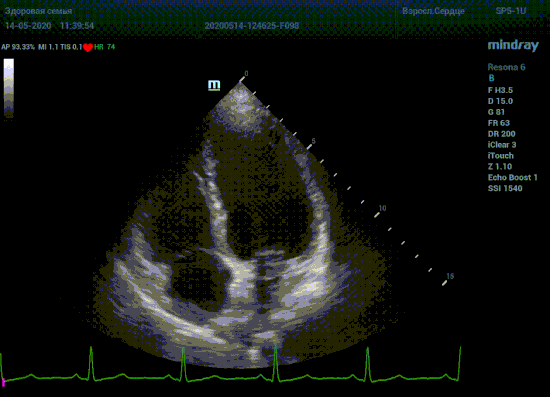

С появлением В режима реализовалась возможность визуализации всех сегментов миокарда из парастернальных и апикальных сечений. Метод Teicholtz в широкой практике сменился методом дисков. Метод дисков, или метод Simpson, позволяет разбить левый желудочек на 20 дисков, с расчетом объема каждого из них. Используя 2 перпендикулярных сечения, апикальные двух и четырех камерное, мы приближаемся к значению реального объема левого желудочка. Исследователь обводит интерфейс эндокард – кровь в фазу диастолы и фазу систолы. Линия простирается от кольца митрального клапана и до кольца митрального клапана, четко разграничивая объем желудочка от предсердия. Для достоверного изменения необходимо использовать ЭКГ канал.

Что могут предложить современные приборы? Приборы нашего времени являются мощными вычислительными машинами, способными обрабатывать полученную информацию даже без помощи человека. Система автоматического вычисления фракции выброса – AUTO EF на приборах серии Resona компании Mindray сделает все за вас. За пару секунд прибор сам отыщет нужную фазу сердечного цикла и произведёт измерение и расчеты, а также покажет график изменения объема в сердечном цикле. От Вас требуется только получить качественное 4С и 2С сечение. Впрочем, прибор всегда оставляет возможность коррекции, если доктор имеет свое мнение на расположение точек планиметрии или момента измерения по ЭКГ каналу.